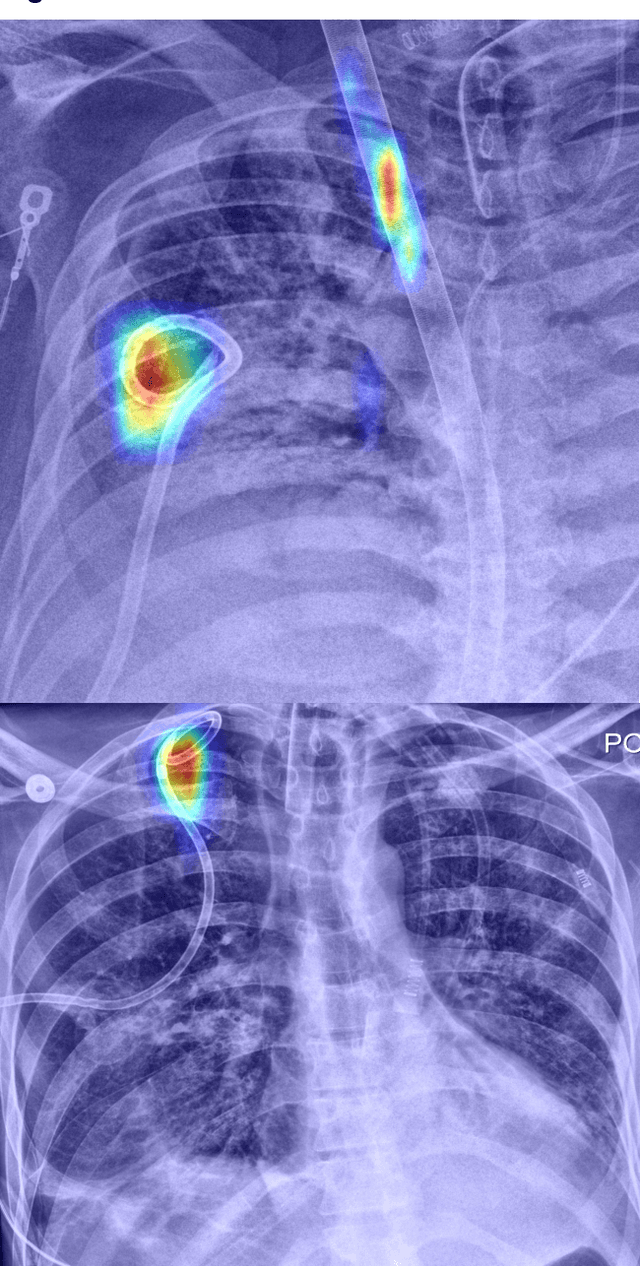

Abstract:Background: Deep learning techniques have achieved high accuracy in image classification tasks, and there is interest in applicability to neuroimaging critical findings. This study evaluates the efficacy of 2D deep convolutional neural networks (DCNNs) for detecting basal ganglia (BG) hemorrhage on noncontrast head CT. Materials and Methods: 170 unique de-identified HIPAA-compliant noncontrast head CTs were obtained, those with and without BG hemorrhage. 110 cases were held-out for test, and 60 were split into training (45) and validation (15), consisting of 20 right, 20 left, and 20 no BG hemorrhage. Data augmentation was performed to increase size and variation of the training dataset by 48-fold. Two DCNNs were used to classify the images-AlexNet and GoogLeNet-using untrained networks and those pre-trained on ImageNet. Area under the curves (AUC) for the receiver-operator characteristic (ROC) curves were calculated, using the DeLong method for statistical comparison of ROCs. Results: The best performing model was the pre-trained augmented GoogLeNet, which had an AUC of 1.00 in classification of hemorrhage. Preprocessing augmentation increased accuracy for all networks (p<0.001), and pretrained networks outperformed untrained ones (p<0.001) for the unaugmented models. The best performing GoogLeNet model (AUC 1.00) outperformed the best performing AlexNet model (AUC 0.95)(p=0.01). Conclusion: For this dataset, the best performing DCNN identified BG hemorrhage on noncontrast head CT with an AUC of 1.00. Pretrained networks and data augmentation increased classifier accuracy. Future prospective research would be important to determine if the accuracy can be maintained on a larger cohort of patients and for very small hemorrhages.